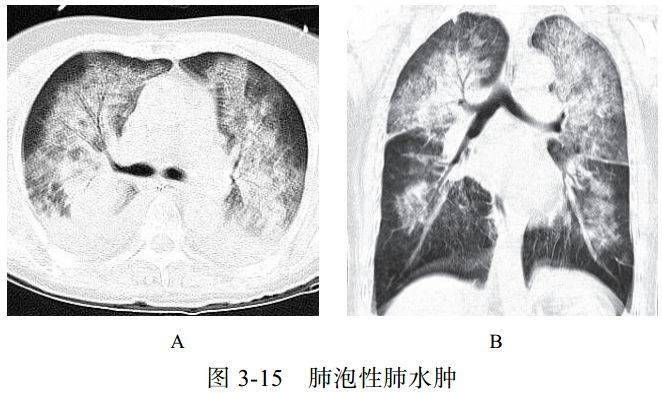

(一)肺泡性肺水肿

肺水肿病理上分为间质性肺水肿和肺泡性肺水肿,严重者常两种情况并存,心源性肺水肿居多。肺泡性肺水肿液体在肺泡内聚集呈片状,肺体积增大,有液体外渗,合并充血时渗液呈红色或棕色,急性期表现为气急、端坐呼吸、咳泡沫白痰或粉红色痰,可闻及湿啰音,可同时出现全身静脉压升高及肝脾大的表现

影像学表现:

(1)典型蝶翼征(图 3-15A),两肺散布大小不等、密度不均、轮廓不清的片状模糊影(图 3-15B),局限性表现为一侧、一叶或局部的密度增高影

(2)心源性肺水肿可见双侧上肺静脉扩张,心影增大,可合并胸腔积液、心包积液